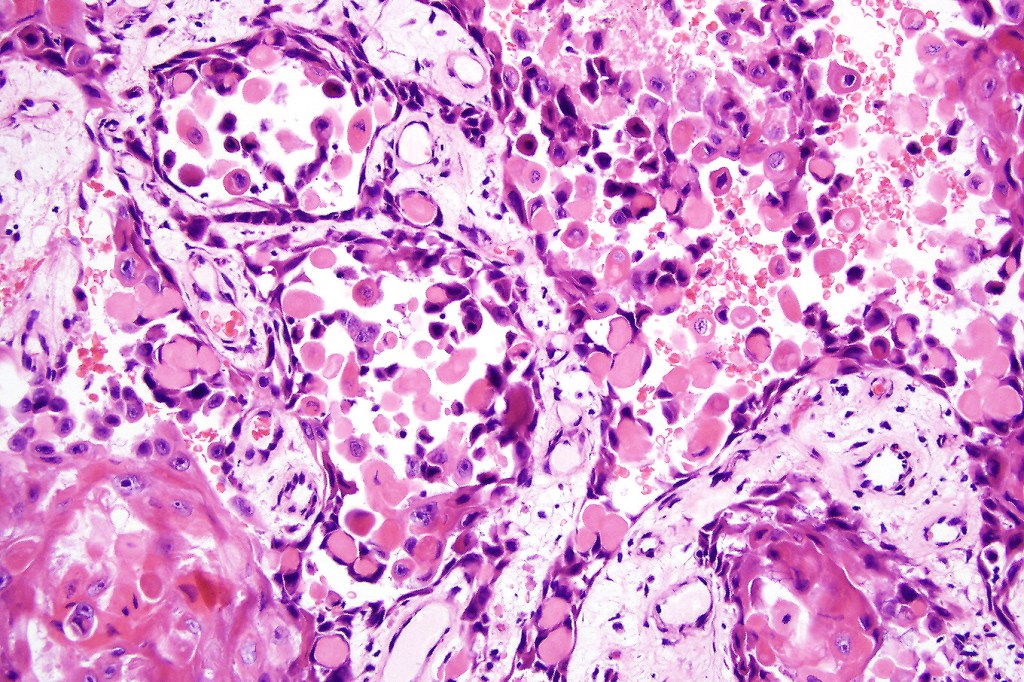

•Variable pleomorphism

•Nucleolar prominence

•Mitoses typically numerous & may be atypical

•Variable perineural infiltration & lymphovascular invasion